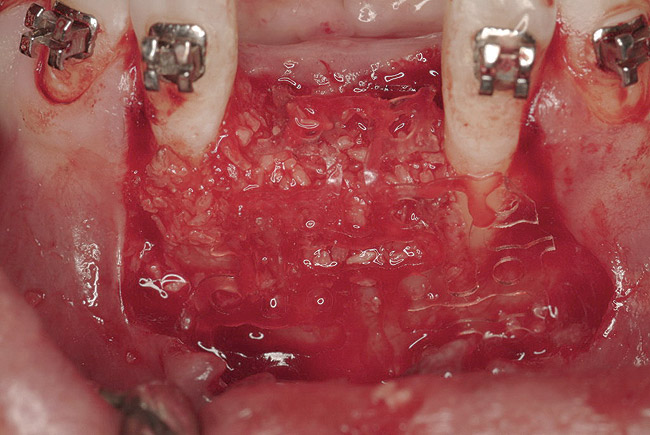

Figure 18  Primary closure was achieved after bilateral sinus grafting and anterior ridge augmentation. The fixed, provisional bridge was then relieved to avoid pressure on the healing sites and recemented.

Figure 18